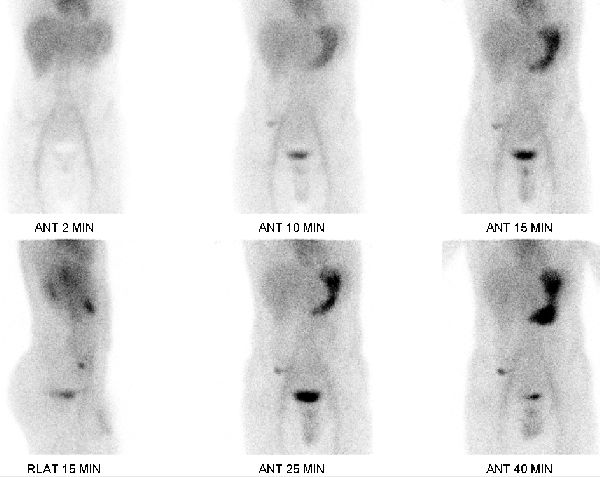

52.梅克爾憩室(Meckel diverticulum)造影檢查,影像中陽性病灶的放射活性強度會與下列何種器官組織的放 射活性相似?

(A)膀胱

(B)胃

(C)小腸

(D)大腸